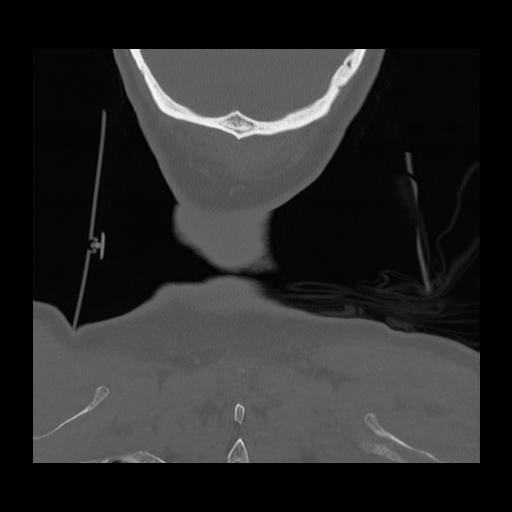

16 HUESO,,Coronal,2.000,HUESO,Coronal,